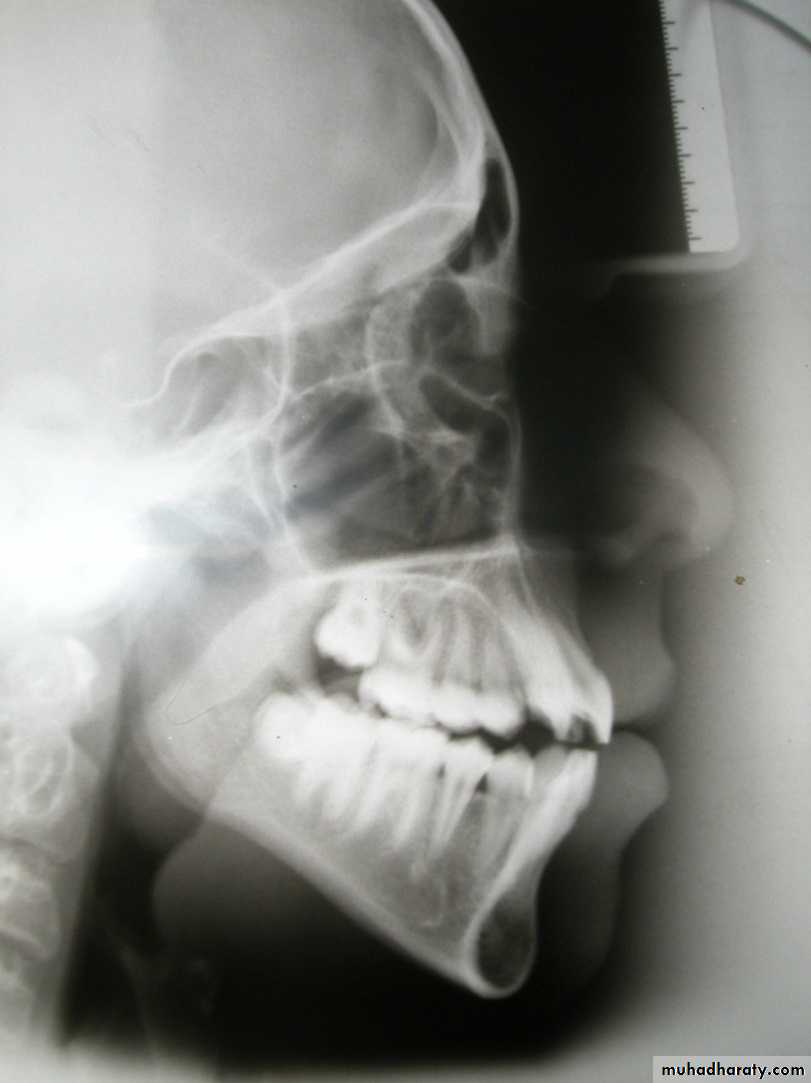

Antero-posterior skeletal relations

SNA angle (82 + 3)

Indicates antero-posterior position of maxillary apical base in relation to the cranial base: Large angle = Prognathic maxilla

Normal angle = Orthognathic maxilla Small angle = Retrognathic maxilla

82

SNB angle (79 + 3)Indicates antero-posterior position of mandibular apical base in relation to the cranial base

Large angle = Prognathic mandible

Normal angle = Orthognathic mandible

Small angle = Retrognathic mandible

80